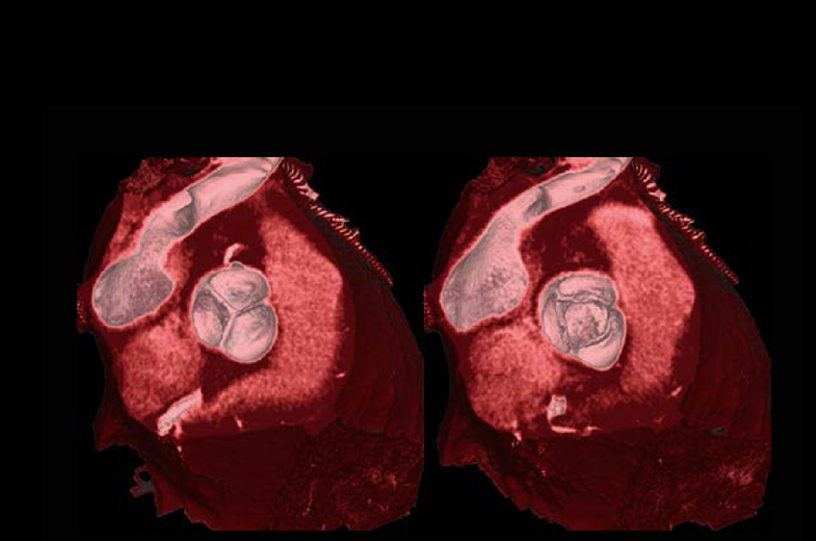

Aortic valve (Cardio StillShot)